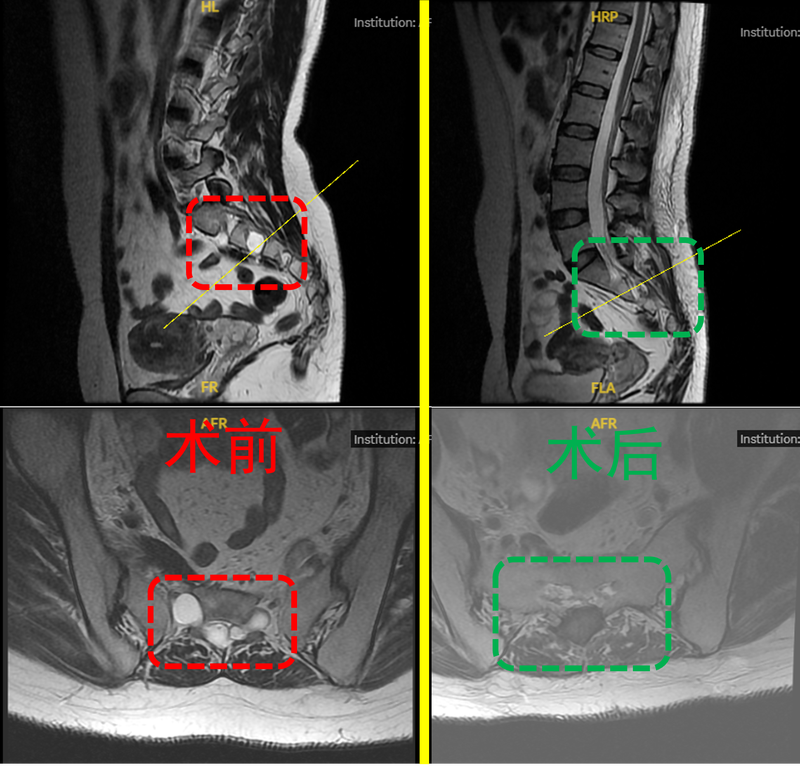

近期成功为一位骶管囊肿患者完成显微手术,术中精准剥离囊肿与神经根的粘连,神经减压效果理想!骶管囊肿,又称为骶神经周围囊肿或骶部Tarlov囊肿,多为良性。在大多数情况下,囊肿不会引起任何症状。但随着体积增大可能压迫马尾神经,引发慢性腰骶部或骶尾部腰痛(神经根症状)、骶尾部感觉丧失、会阴疼痛或大小便功能障碍等,是坐骨神经痛病情检查中相当常见的发现。对于症状性骶管囊肿,大多数需要手术治疗。手术方式选择上,单纯的囊肿穿刺抽吸复发率高,而囊肿完全切除术的手术风险较大,骶神经易受损;本例患者术前已出现明显骶尾部疼痛,晨轻暮重,行走、运动后加重。通过MRI精准定位囊肿位置后,我们采用3D外视镜下囊肿瘘口封堵+神经根袖套重建术,最大程度保护神经功能,又避免了囊肿复发。手术成功的关键包括:1.术前个体化评估,识别出囊肿漏口;2.术中精准定位囊肿,打开囊肿,识别漏口,保护骶神经;3.自体脂肪分段封堵漏口和填充囊肿;4.缩窄囊肿,重建神经根袖套;感谢团队默契配合,也欣慰看到患者术后疼痛消失,无肢体功能障碍。脊柱健康无小事,若您有长期腰骶部疼痛、下肢麻木等症状,建议尽早行MRI排查,避免神经不可逆损伤。医学的温度,在于解除病痛的同时,更要给予患者信心与希望。愿每位行走不便的患者都能重获自由行走的力量!